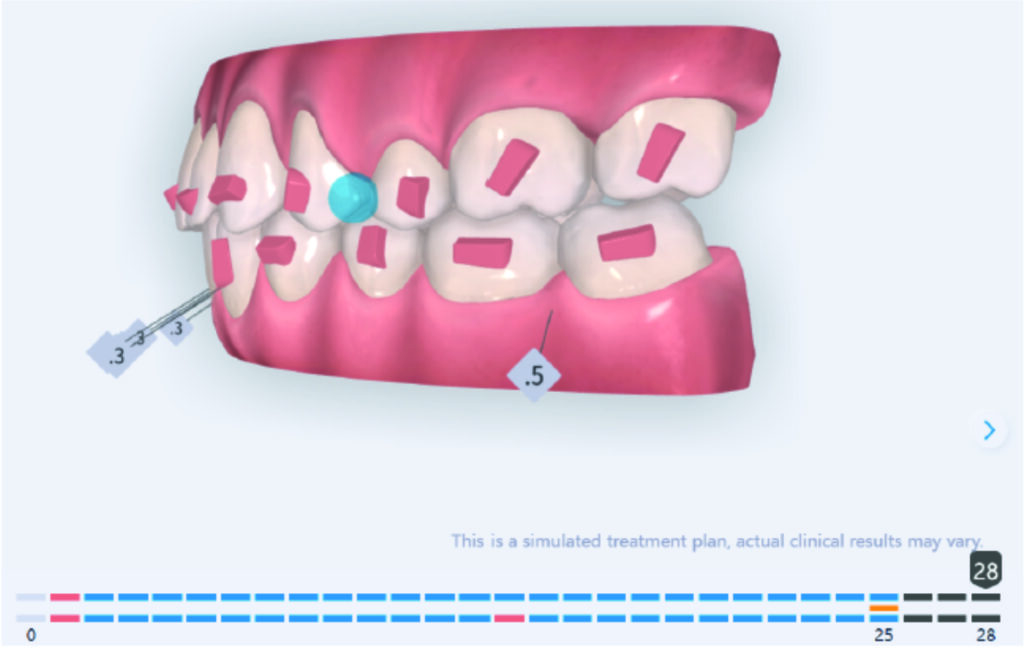

Distalization in segment 1 to Class I and derotation of 16, move upper central line to fit lower central line.

Derotation 26. IZC anchorage.

A 1.5 mm deviation of the upper dental midline to the patient’s left was noted, along with a slight mandibular midline shift to the right, likely due to asymmetrical mandibular growth observed in the facial structure. Severe mesial rotations of teeth 16 and 26 were evident in the initial records. As derotation of 16, 26, 17, and 27 progressed up to aligner 16, the premolars in segments I and II moved distally, resulting in a bilateral Class I relationship, as intended in the initial treatment plan.

Derotation of 16 26 allowed Class II correction.

Vertical vector of elastic traction on buttons and IZC helped with the open bite correction.

No sequential distalization for Class II tendency correction was performed due to skeletal anchorage. Lingual attachments were used to improve aligner grip and control tooth movement, as small, angulated lower incisors are difficult to move due to limited anatomy.

An infrazygomatic crest (IZC) screw with force applied between the upper premolars produces a clockwise rotation of the maxillary occlusal plane. This movement aids in closing the anterior open bite and improves upper incisor display. IZC screws with elastics also enable planned intrusion of the upper molars by 1 mm. Because mandibular derotation after upper posterior correction is difficult to predict, anterior distalization and midline correction were performed in the later stages of treatment.